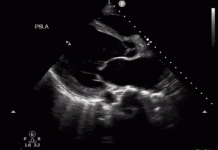

Standart ultrasonografik inceleme için farklı frekanslara sahip lineer, konveks ve sektör problar kullanılmalıdır. Probun frekansı arttıkça penetrasyon özelliğinin azalacağı buna karşılık rezolüsyonunun artacağı bilinmelidir. Yani yüksek frekanslı problar (lineer prob) yüzeye yakın dokuları daha detaylı ve net görmemizi sağlarken (düşük torasik çap ve pnömotoraksın değerlendirilmesi), derin dokulara penetrasyonları kötü olduğu için akciğer ve batın organları için tercih edilmezler. Daha çok göğüs duvarı, plevra, periferik lenf bezleri gibi bölgelerin değerlendirilmesinde kullanılırlar. Buna karşılık daha düşük frekanslı problar (konveks prob) derin dokulara penetrasyon özelliklerinin iyi olması nedeniyle batın içi organların ve akciğer parankim patolojilerinin değerlendirilmesinde tercih edilir. Sektör probun (phased array) özelliği ise ses dalgalarının tek bir noktadan çıkıp, fan şeklinde etrafa yayılması sayesinde interkostal aralıktan rahatlıkla kalp ve akciğer alanlarını gösterebilmesidir. Bu sayede kardiyak değerlendirme için kullanılan problardır.

5. Perikardiyal Tamponad (E-FAST parçası)

-

Perikardiyal efüzyon

Sağ ventrikül veya sağ atriyum diyastolik kollapsı

IVC dilatasyonu ve inspirasyonla kollabe olmaması